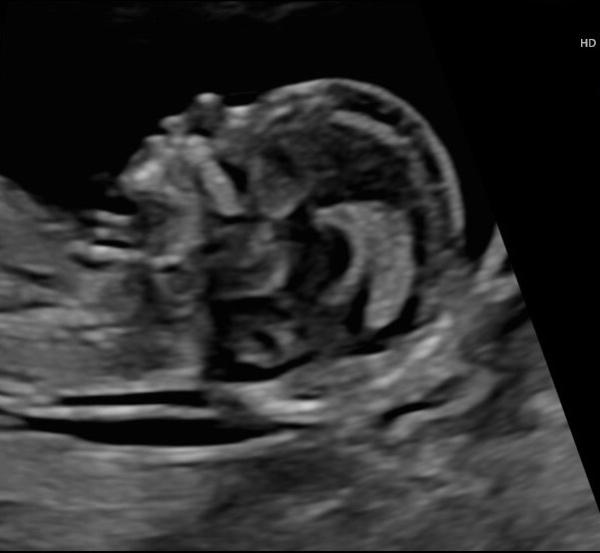

Guten Morgen, ich bin heute 13+0. gestern hatte ich den Ultraschall im Rahmen der Pränataldiagnostik. Es war wirklich faszinierend und zum Glück alles unauffällig Ich fand es toll das Baby so lange beobachten zu können und trotzdem habe ich es immer noch nicht wirklich realisiert, dass wir in wenigen Monaten zu dritt sein werden. Kommt es euch auch noch so unwirklich vor? So langsam wissen es auch alle Freunde, das macht es ein bisschen präsenter, aber es kommt mir immer noch so unwirklich vor. Ich hoffe es kommt noch, wenn der Bauch wächst (worauf ich jeden Tag warte). Ansonsten hatte ich von Beginn der Schwangerschaft an kaum Probleme, abgesehen von Müdigkeit. Seit einer Woche hat diese aber extrem zugenommen, ich könnte den ganzen Tag schlafen, außerdem leide ich unter leichter Übelkeit... dabei sollte doch ab der 12.ssw alles besser und nicht schlechter werden Würde mich über eure Erfahrungen freuen

Bild zu Geht es euch ähnlich? - Forum für Januar - Mamis